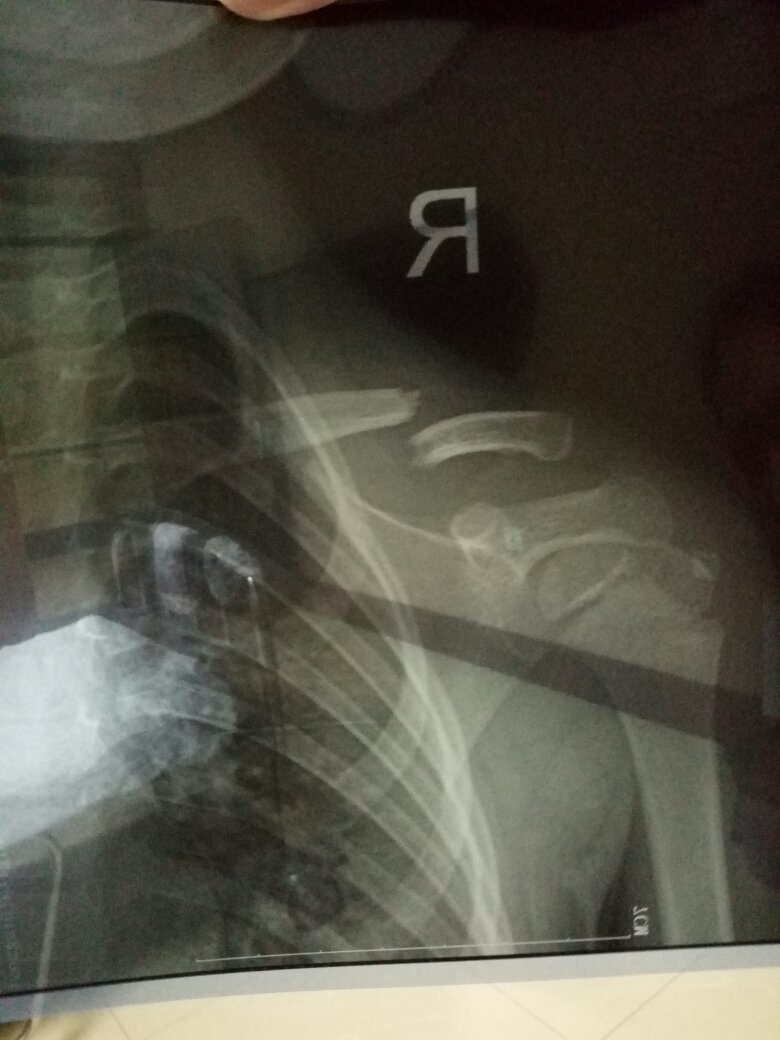

3岁的宝宝锁骨骨折错位了断端分离,保守治疗可以恢复正常吗 点击展开 147*****788_oO8p 2016-07-02 20:29 满意回答 这个真不一定了。错位比较明显了。问你的主管医生吧 rr9284 2016-07-02 20:32 宝宝知道提示您:回答为网友贡献,仅供参考。 相关问题 四岁小孩右边锁骨骨折错位,保守治疗有哪些方案更稳妥? 锁骨骨折完全错位没手术,56天时去医院复查X线报告未见… 我家宝宝二岁了,20号从车上摔下来 右肩着地,当时她老哭 我就去医院拍了X片,右锁骨骨折 没